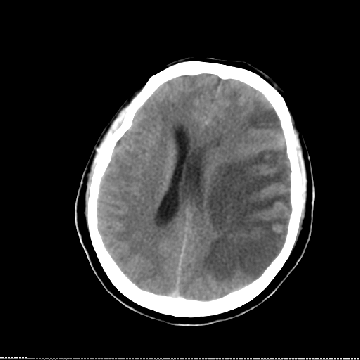

患者,女,56岁,因突发失语右侧肢体无力3h入院,入院查体:神志清楚,言语对答切题,但含糊,右侧鼻唇沟变浅,伸舌右偏,右侧肢体肌张力正常,右侧肌力4级,无明显感觉障碍,腱反